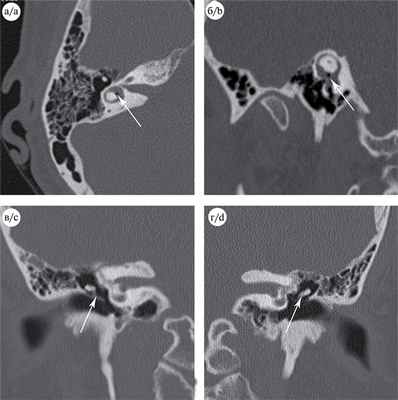

На СКТ височных костей (рис. 2) Рис. 2. СКТ височных костей в аксиальной (a) и сагиттальной (б) плоскостях демонстрирует присутствие маленького пузырька воздуха в преддверии лабиринта (стрелки); на СКТ во фронтальной плоскости (в, г) определяется изменение положения рукоятки молоточка (обозначено стрелками) справа (в) и нормальное ее положение слева (г). обнаружены признаки пневмолабиринта и изменение положения рукоятки молоточка справа.